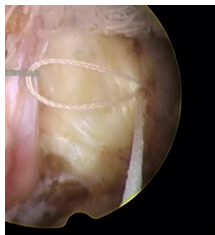

縫合后的纖維環(huán),將外翻的纖維環(huán)向椎間隙人包埋,表面光滑平整,椎間盤內(nèi)部不再與椎管相通,椎間盤內(nèi)的髓核炎性介質(zhì)不易外滲,減少了對(duì)神經(jīng)根的刺激,術(shù)后疼痛減輕。并且進(jìn)行纖維環(huán)縫合的病例不需要過多切除椎間盤內(nèi)的髓核,對(duì)維持椎間盤的功能和脊柱的穩(wěn)定性有一定的作用。

一次性纖維環(huán)縫合器術(shù)式:

椎間盤髓核摘除+纖維環(huán)修復(fù)術(shù)是目前治療椎間盤突出癥最有效、最安全的微創(chuàng)方法之一。不僅在最大程度上保留椎間盤的功能、減少術(shù)后瘢痕的形成、降低髓核炎性介質(zhì)對(duì)神經(jīng)根的刺激,還避免了二次手術(shù)帶來的痛苦以及經(jīng)濟(jì)負(fù)擔(dān)。